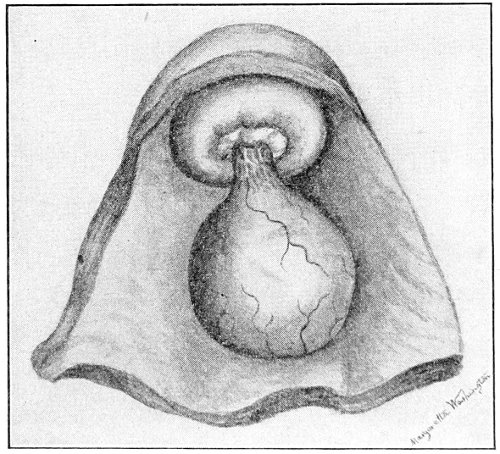

Cysts of the Vulvo-vaginal Glands.—Cysts may 41 occur in the duct of the vulvo-vaginal gland or in the gland itself. Cysts of the duct are small—about the size of a chestnut. They are situated superficially, lying immediately under the mucous membrane of the vagina at the base of the labium minus.

Fig. 18.—Cyst of the right vulvo-vaginal gland (Hirst).

Cysts of the gland may be unilocular if formed at the expense of a single lobule of the gland, or multilocular if several lobules enter into their formation. These cysts may attain the size of the fetal head (Fig. 18).

Cysts of the gland or of the duct are formed by retention of the cyst-contents. The retention is due to occlusion of the duct, usually the result of inflammation. In some cases the duct remains pervious, and the retention is due to the altered character of the secretion of the gland, which becomes too viscous to pass, except under unusual pressure, along the duct.

These cysts contain clear yellow or chocolate-colored 42 fluid. The diagnosis of cyst of the vulvo-vaginal gland is usually not difficult. If we are in doubt in regard to the fluid character of the tumor, this may be determined with the exploring-needle.

Inguinal hernia, hydrocele of the canal of Nuck, cysts of the round ligament, and sacculated cysts of old hernial sacs may be mistaken for cysts of the vulvo-vaginal glands. In such cases, however, the tumor lies more in the upper and outer part of the labium majus, and extends to, and may be connected with, the external inguinal ring.

Cysts of the vulvo-vaginal glands should be treated by free incision and packing, or by extirpation. If the sac is emptied by the aspirator or by a small incision, it will refill. The best method is to extirpate the cyst. In case there has been no inflammatory action binding the cyst to surrounding structures, extirpation without rupture is easy. If rupture occurs, the cyst-wall may be dissected off with the knife or removed with the curved scissors. The wound may be immediately closed with deep and superficial sutures.